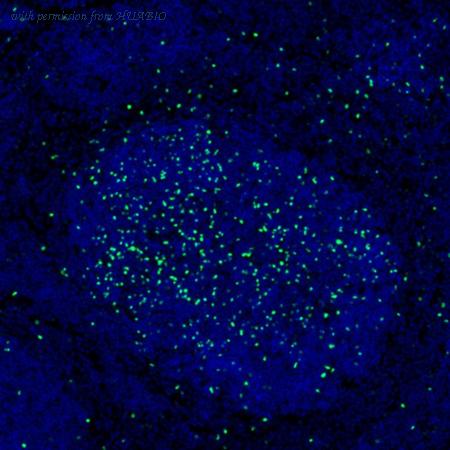

image 1 :

mIHC analysis of mouse spleen tissue (Formalin/PFA-fixed paraffin-embedded sections) with Rabbit anti-FOXP3 antibody (IRS053) at 1/100 dilution. The immunostaining was performed with the IRISKitCmTSA Kit (900808). Heat mediated antigen retrieval with Tris-EDTA buffer (pH 9.0) for 30 mins at 95℃. DAPI (blue) was used as a nuclear counter stain. Image acquisition was performed with Olympus VS200 Slide Scanner.